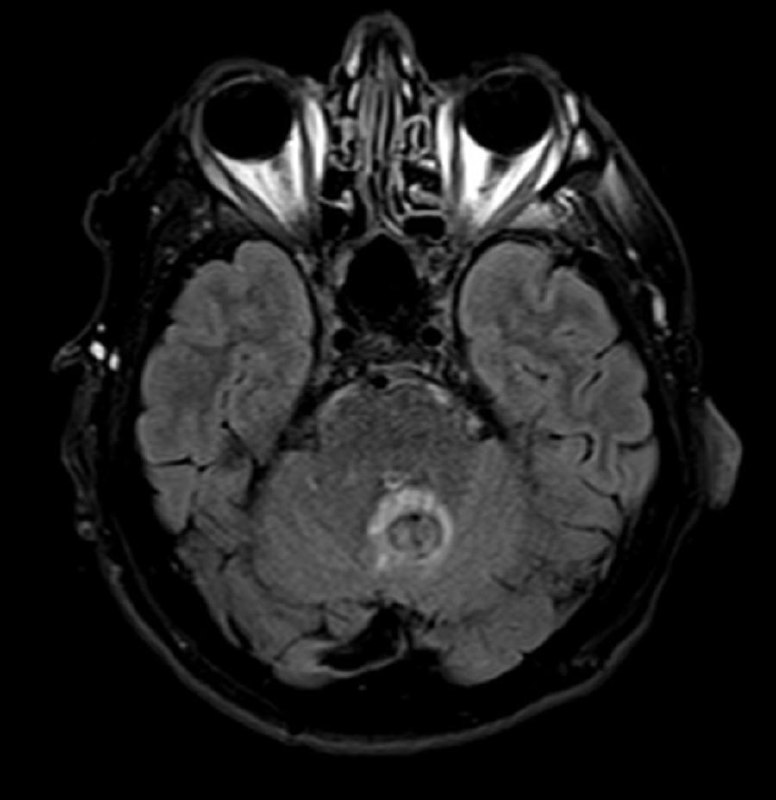

Пациент 35 лет. Жалобы на онемение правой руки. Других жалоб нет.

в декабре 2020 удалена менингиома, а теперь - вот так